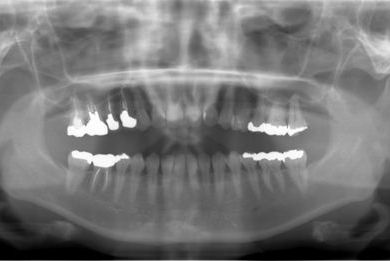

抜歯即日スピードインプラント治療

| 性別/年齢 | 女性 / 39歳 | ||||||||||||||||||||||||||||||||

| 主訴 | 左前歯の虫歯治療を希望。 | ||||||||||||||||||||||||||||||||

| 治療内容 | インプラント1本(抜歯即日スピードインプラント)、メタルボンドセラミック1本 | ||||||||||||||||||||||||||||||||

| 総治療費 | 458,588円 | ||||||||||||||||||||||||||||||||

| 治療期間 | 1年0ヶ月 |